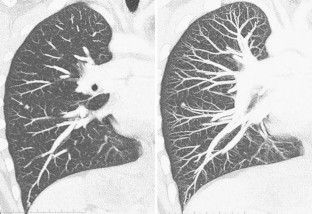

Fig. 1

Fig. 2